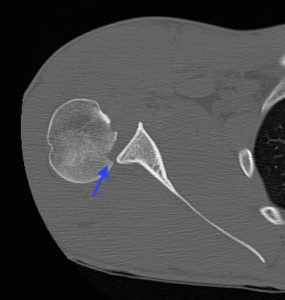

Posterior Shoulder Dislocation, CT, Annotated. JETem 2017

Irreducible Traumatic Posterior Shoulder Dislocation